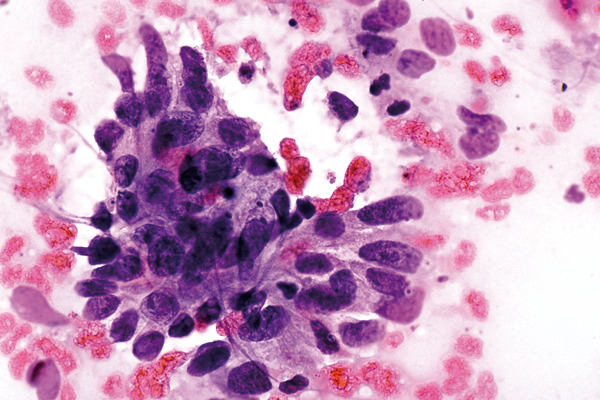

März

richtige Antwort:

c. Adenocarcinom der Endozervix

- vergrößerte Kerne und deutliche Nucleolen

- hohe Zellzahl an Drüsenzellen

- Zellen locker gelagert, teilweise auch in azinärer oder papillärer Anordnung

- unterschiedliche Größe der Zellen und Zellkerne

- Kerngröße steigt bei zunehmender Entdifferenzierung der Zellen